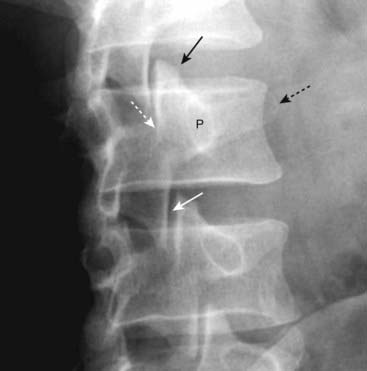

imageIn general, spondylolisthesis can occur if there are bilateral breaks in the pars interarticularis (spondylolytic spondylolisthesis) or if there is osteoarthritis of the facet joints (degenerative spondylolisthesis) (Fig. 24-11).

image Facet osteoarthritis may be associated with spondylolisthesis (degenerative spondylolisthesis) through a complex interaction between the ligaments, disks, and facet joints wherein disease in any one (or more) of these components increases the stress on the others which can lead to spondylolisthesis.

image In degenerative spondylolisthesis, there is no break in the pars interarticularis. The degree of spondylolisthesis is usually less from this etiology than in those with spondylolisthesis from spondylolysis. Degenerative spondylolisthesis is more common in women and usually affects the L4-L5 disk space.

Posterior slippage of one vertebral body on the body below (retrolisthesis) may also occur from facet osteoarthritis.

The lateral (sagittal) view is best at demonstrating spondylolisthesis, which will be visible as slippage of one vertebral body on the body below, usually anteriorly.

If the slippage approximates 25% of the anteroposterior (AP) diameter of the vertebral body below, it is called a grade I spondylolisthesis. If the slippage approximates 50% of the AP diameter of the vertebral body below, it is called a grade II spondylolisthesis, and so on for grade III and grade IV (see Fig. 24-11).

Figure 24-11 Spondylolytic spondylolisthesis (A) and degenerative spondylolisthesis (B).

A, There is forward slippage of L4 on L5 equal to about half the AP diameter of L5 (solid black arrow), so this is classified as a Grade II spondylolisthesis. Spondylolysis is present (solid white arrow) that has allowed the slip to take place. There are also incidental large osteophytes at the corners of the vertebral bodies (dotted black arrow). B, Facet osteoarthritis (solid white arrows) may be associated with spondylolisthesis through a complex interaction between the ligaments, disks, and facet joints. In degenerative spondylolisthesis, there is no break in the pars interarticularis and the degree of spondylolisthesis (solid black arrow) is usually less in this group than in those with spondylolisthesis from bilateral spondylolysis. The L4-L5 disk space is most commonly affected.